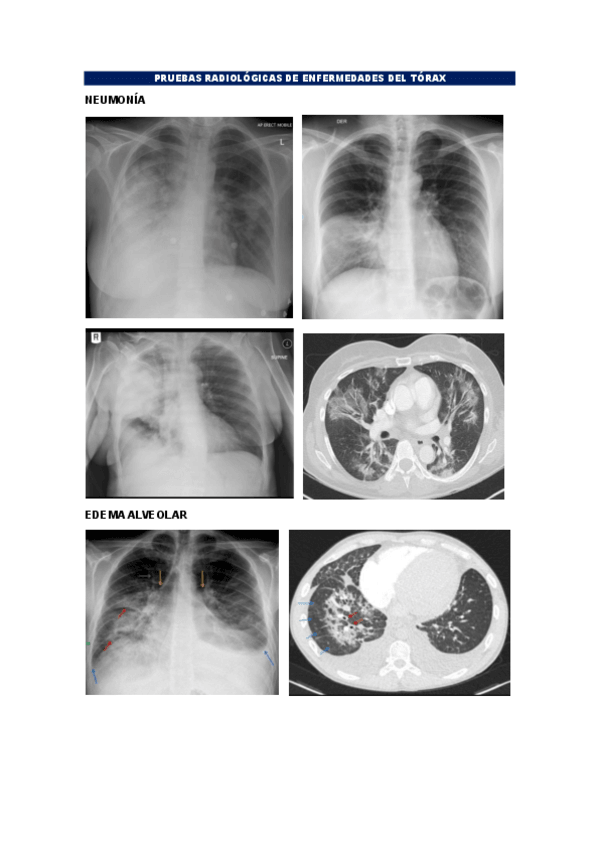

Prácticas tórax y abdomen

He publicado nuevos practicas de 2º Radiologia General: Prácticas tórax y abdomen

Practica-2-torax.pdf